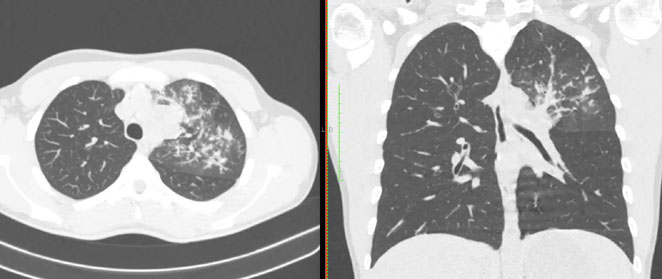

4.3. ЛУЧЕВАЯ ДИАГНОСТИКА COVID-19

Методы лучевой диагностики применяют для выявления COVID-19 пневмоний, их осложнений, дифференциальной диагностики с другими заболеваниями легких, а также для определения степени выраженности и динамики изменений, оценки эффективности проводимой терапии.

К методам лучевой диагностики патологии ОГК пациентов с предполагаемой/установленной COVID-19 пневмонией относят:

- Компьютерную томографию легких (КТ),

КТ имеет высокую чувствительность в выявлении изменений в легких, характерных для COVID-19. Применение КТ целесообразно для первичной оценки состояния ОГК у пациентов с тяжелыми прогрессирующими формами заболевания, а также для дифференциальной диагностики выявленных изменений и оценки динамики процесса. КТ позволяет выявить характерные изменения в легких у пациентов с COVID-19 еще до появления положительных лабораторных тестов на инфекцию с помощью МАНК. В то же время, КТ выявляет изменения легких у значительного числа пациентов с бессимптомной и легкой формами заболевания, которым не требуется госпитализация. Результаты КТ в этих случаях не влияют на тактику лечения и прогноз заболевания при наличии лабораторного подтверждения COVID-19. Поэтому массовое применение КТ для скрининга асимптомных и легких форм болезни не рекомендуется.

15. Рекомендации по формированию описаний и оценке изменений в легких и ОГК при имеющейся/подозреваемой пневмонии COVID-19 представлены в Приложении 1.